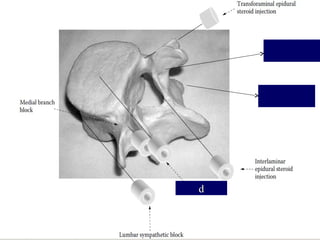

Facet joint injection orRF Medial branch block or RF Transforaminal epidural injection Intradiscal procedure: Discography Provacation test Ozone discectomy Laser discectomy Percutanous disc Epiduroscopy and adhesolysis Epidural injection

TRANSFORAMINAL ROOT BLOCK  Highlyselective  Diagnostic as well as therapeutic  Delivers medicine to the floor of spinal canal

FACET INJECTION  Facetfor back pain  Not for radicular pain  May act as epidural in 40% of cases